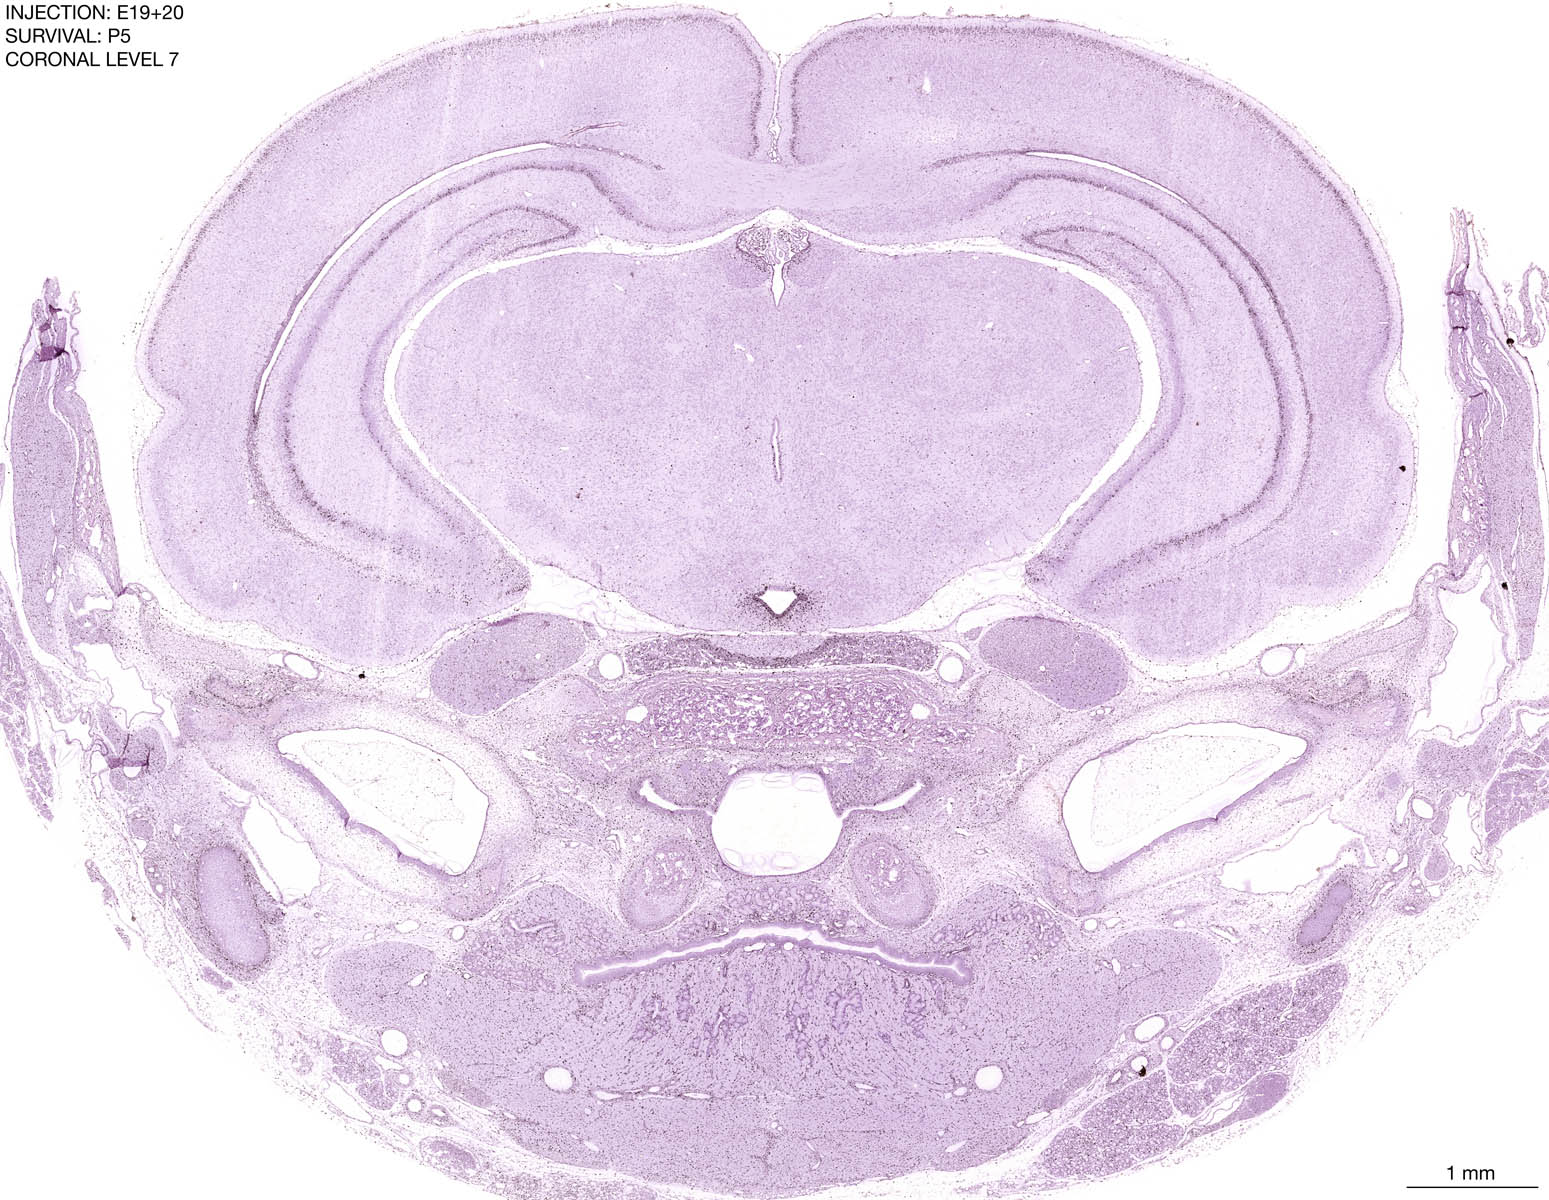

E19+20 P5 Survival The images below are from the brain of a rat that was exposed to tritiated thymidine on E19+20 and survived to P5. Download: Large | High Res Download: Large | High Res Download: Large | High Res Download: Large | High Res Download: Large | High Res Download: Large | High Res Download: Large | High Res Download: Large | High Res Download: Large | High Res Download: Large | High Res Download: Large | High Res Download: Large | High Res Download: Large | High Res Download: Large | High Res Download: Large | High Res Download: Large | High Res Download: Large | High Res Download: Large | High Res Download: Large | High Res Download: Large | High Res Download: Large | High Res Download: Large | High Res Download: Large | High Res Download: Large | High Res Download: Large | High Res Download: Large | High Res Download: Large | High Res Download: Large | High Res